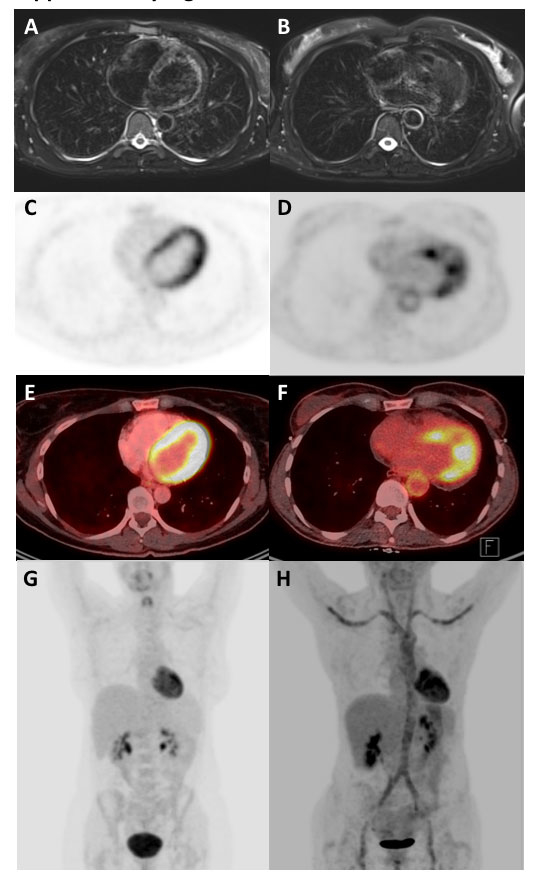

Figure 5 Comparison of vasculitis and normal findings. Panels A, C, E, and G are from a patient without vasculitis. Panels B, D, F, and H show the same patient as in figure 3. T2-weighted fat-suppressed magnetic resonance imaging (PROPELLER sequence) (A, B), 18F-fluorodeoxyglucose positron emission tomography attenuation corrected (C, D) fusion (E, F) and maximum intensity projection reconstruction (G, H) are shown.